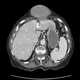

Herniation of liver

Diaphragmatic rupture (also called diaphragmatic injury or tear) is a tear of the diaphragm, the muscle across the bottom of the ribcage that plays a crucial role in respiration. Most commonly, acquired diaphragmatic tears result from physical trauma. [Source: Wikipedia ]